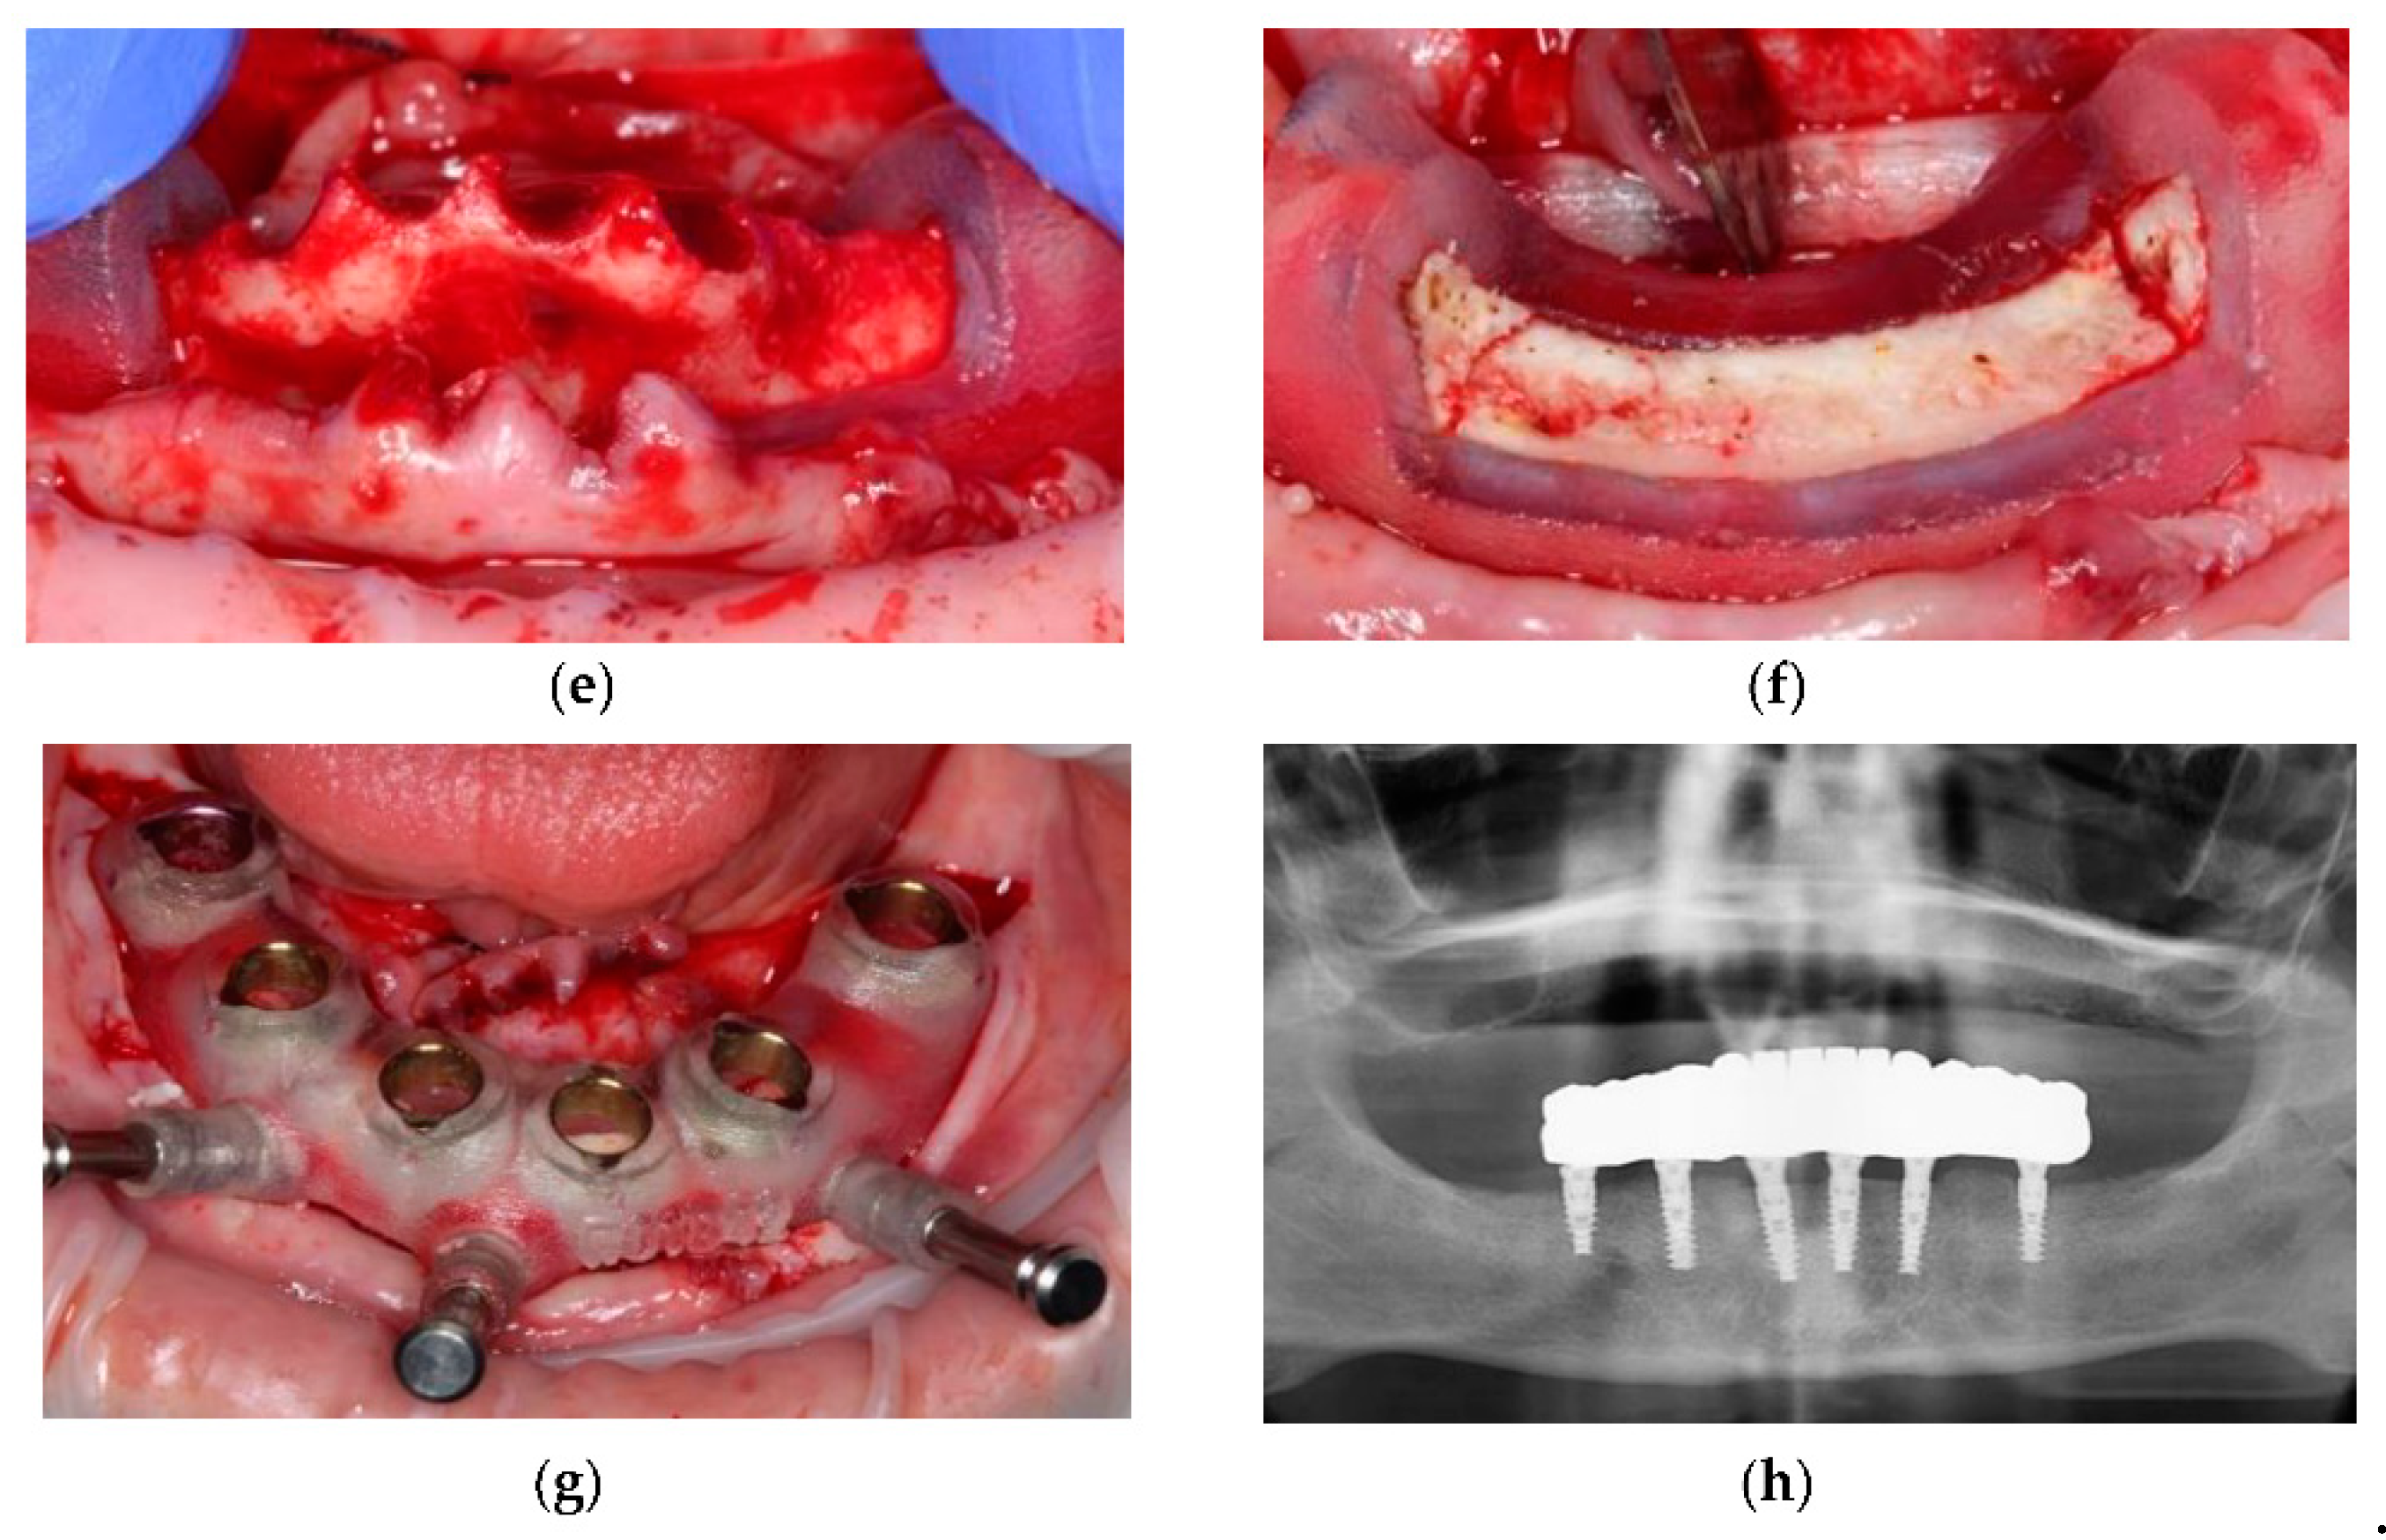

- Costa, A.J.M.; Teixeira Neto, A.D.; Burgoa, S.; Gutierrez, V.; Cortes, A.R.G. Fully Digital Workflow with Magnetically Connected Guides for Full-Arch Implant Rehabilitation Following Guided Alveolar Ridge Reduction. J. Prosthodont. Off. J. Am. Coll. Prosthodont. 2020, 29, 272–276. [Google Scholar] [CrossRef]

- Faeghi Nejad, M.; Proussaefs, P.; Lozada, J. Combining guided alveolar ridge reduction and guided implant placement for all-on-4 surgery: A clinical report. J. Prosthet. Dent. 2016, 115, 662–667. [Google Scholar] [CrossRef] [PubMed]

- Beretta, M.; Poli, P.P.; Tansella, S.; Maiorana, C. Virtually guided alveolar ridge reduction combined with computer-aided implant placement for a bimaxillary implant-supported rehabilitation: A clinical report. J. Prosthet. Dent. 2018, 120, 168–172. [Google Scholar] [CrossRef]

| Stackable Guides [10,11,32,33] | Case report [11] | Yes | CBCT and computer software | Accurate reduction using specialized software utilising CAD/CAM and 3D-Dicom data | |

| Magnetically Connected Guides [36] | Technical study | Yes | Intra-oral scanner, clinical photographs, CBCT, CAM/CAM | Improved stability utilizing the magnets-embedded PMMA prosthesis | - |